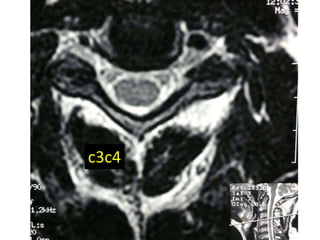

c3c4

47 year old woman with 6 month h/o neck stiffness and pain with

left UE paresthesias into

The elbow forearm and hand especially IF/thumb